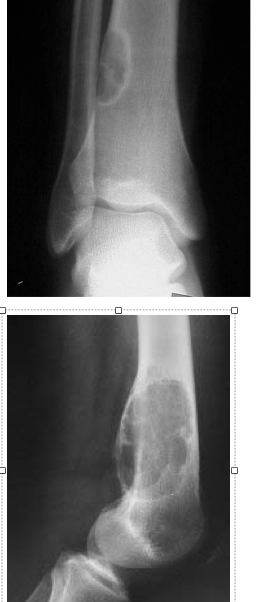

Describe the lesion. Differential? Diagnosis? Associated conditions?

Non-ossifying fibroma